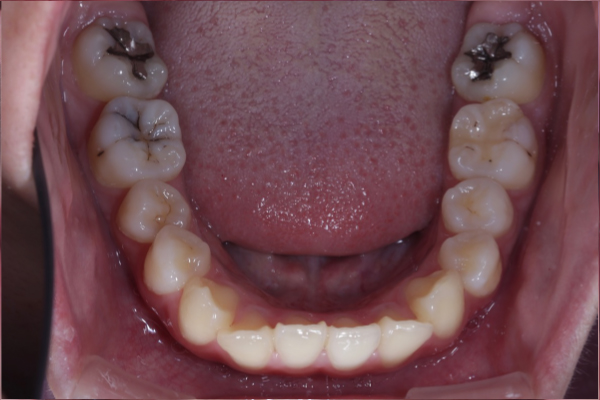

右上の乳犬歯が長期間残っていることを気にされ来院されました。

歯並び自体の大きな乱れはありませんでしたが、永久歯(犬歯)が萌出していない状態を心配され、精密検査を希望されました。

検査の結果、上顎犬歯が顎骨内に埋伏していることを確認しました。

自然萌出は困難と判断し、矯正治療による牽引で歯列内へ誘導する治療を計画しました。

BEFORE